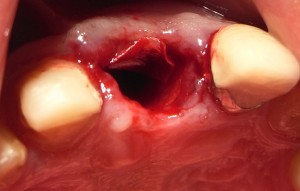

抜歯

抜歯

抜歯後の穴。唇側の骨はなくなってしまっている。吸収性の人工膜を設置。

抜歯後の穴。唇側の骨はなくなってしまっている。吸収性の人工膜を設置。